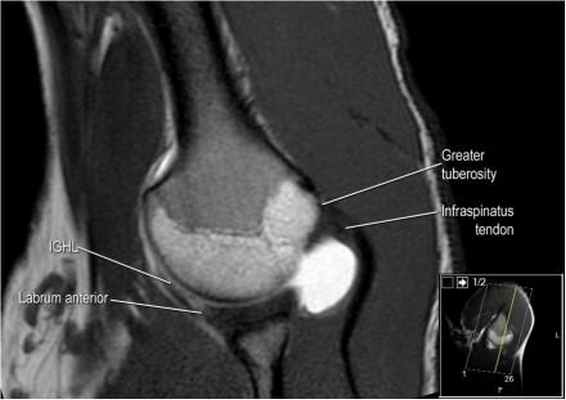

а бРис. 1. МР-артрография. МР-томограммы ПС: а – корональная плоскость, T1 TSE; б,в – аксиальная плоскость T1 TSE, FS T1 TSE

Протоколы нативного МР-исследования и МРА плечевого сустава включали получение трех взаимно перпендикулярных проекций (косой коронарной, косой сагиттальной и аксиальной). Нативное исследование проводилось с использованием следующих импульсных последовательностей: TSE PD SPAIR – изображения, взвешенные по протонной плотности, с эффектом подавления сигнала от жировой ткани; TSE_T1W-Т1 взвешенном изображении (ВИ) в режиме турбо-спин эхо; FFE_T2W-Т2 ВИ в режиме градиентного эхо (табл.1). МРА проводили в режиме TSE_T1W, а также с использования эффекта жироподавления – TSE_T1W SPIR (табл.2, рис.1). Исследование проводилось через 15 минут после введения контраста и выполнения пациентом маятникообразных движений верхней конечностью.

Изображение задних отделов плечевого сустава.

Отображены надостная, подостная и малая круглая мышцы и их сухожилия. Все они прикрепляются к большому бугорку плечевой кости. Сухожилия и мышцы манжеты вращателей участвуют в стабилизации плечевого сустава во время движения. Без манжеты вращателей головка плечевой кости частично сместилась бы из суставной впадины, уменьшив силу отведения дельтовидной мышцы (мышцы вращательной манжеты координирует усилия дельтовидной мышцы). Повреждение манжеты вращателей может привести к смещению головки плечевой кости кверху, в результате вызвая высокое стояние головки плечевой кости.